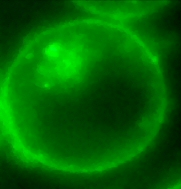

- Biomedical engineering applications including studies of nanosecond pulsed electric fields applied to cancer cells in vitro and tumors in vivo. This work, in collaboration with the Alfred Mann Institute, includes biophotonic studies of the effects of intense nanosecond electric fields on various cancer cell lines. Animal studies conducted with catheter-based pulsed power delivery systems are showing promise for therapies for potential cancer therapies.

Dr. Gundersen's research activities are in applied plasma science with applications to combustion, pollution control, and pulsed power; quantum electronics, semiconductor devices and physics, and biophysics. Current interests include applications of pulsed power to biological cells, and investigation of cellular responses to pulsed electrical fields.